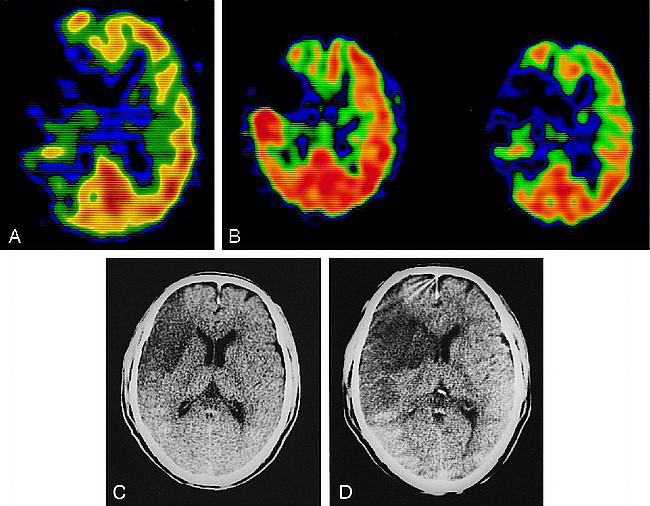

Case 2: 69-year-old man with atrial fibrillation and sudden onset of left-sided hemiparesis.

A, 99mTc-HMPAO SPECT image 7.5 hours after the onset of stroke shows hypoactivity in the right parietal lobe.

B, Both 99mTc-HMPAO (left) and 99mTc-ECD (right) SPECT images obtained 12 hours after the initial study depict hyperactivity in the right parietal lobe.

C, Follow-up CT scan does not show any abnormality.

Twelve hours after the initial SPECT study, we obtained 99mTc-HMPAO and 99mTc-ECD SPECT images using the same procedure as described for case 1. Both SPECT studies depicted hyperactivity in the right parietal lobe (Fig 2B). Subsequent cerebral angiography showed complete recanalization of the right MCA. A follow-up CT scan did not show any abnormality in the hyperactive area (Fig 2C).